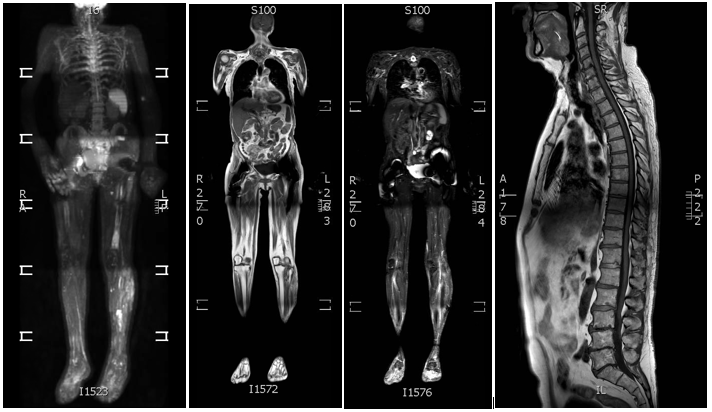

Full Body MRI station placement example for technologist reference

MRI - full body image example for technologists

MRI Full Body MSK - Brain image for technologist reference

FULL BODY MSK IMAGES FOR POST PROCESSING INSTRUCTIONS FOR TECHNOLOGISTS